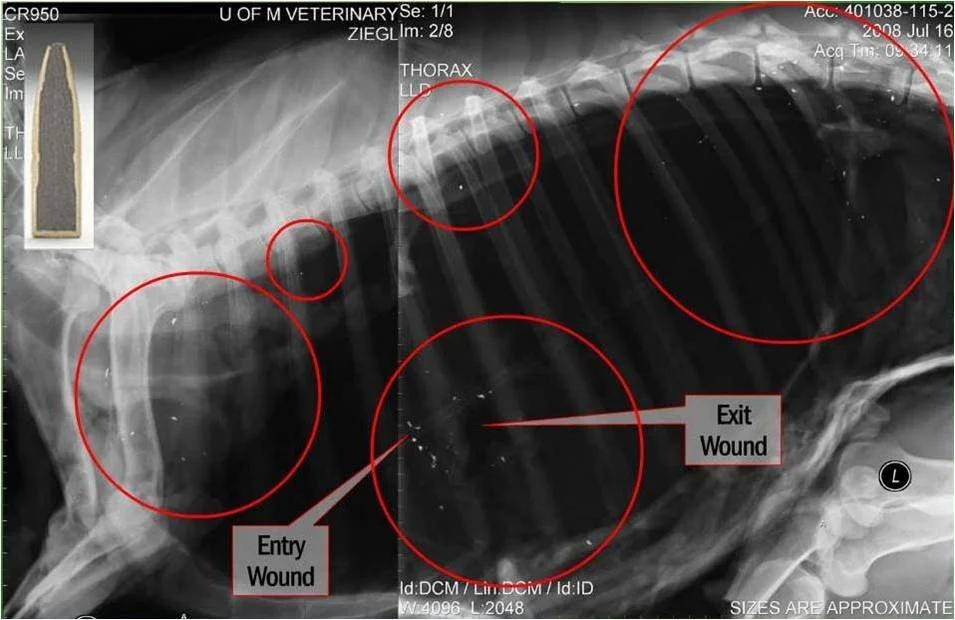

The Evidence: What X-Rays Reveal

Radiographic imaging provides undeniable visual evidence of lead contamination in both harvested game and the wildlife that scavenges remains.

Lead Fragments

X-rays of an animal shot with a lead bullet show widespread fragmentation — dozens of tiny lead particles scattered throughout the body cavity, far beyond the wound channel.